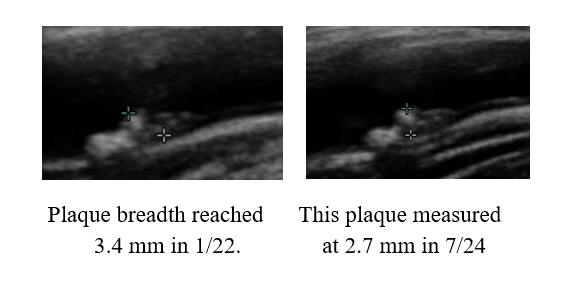

I began working with PM in '07, 14 years ago. Chest tightness, then associated with a non-threatening stress test, resolved following 20 IV EDTA treatments. PM's IMT of 0.678 was below-average-for-age; carotid plaque was not identified. PM began a program of risk factor reduction, but we could not dent PM's LDL elevation (150-180 mg/dl), at least not with treatments that PM could tolerate. PM's IMT rose between '08 and '22, at an average rate of 0.007 mm per year, but calcific carotid bulb plaque had developed over this interval. PM received two months of cyclodextrin in '23, as a proactive preventative, our theory being that if we can't lower PM's circulating lipids, perhaps we could make up by pulling lipids out of the vascular wall. PM's IMT was repeated in 1/25, and demonstrated active IMT regression, at a rate of 0.02 mm per year (a lot). Thus PM's predisposition towards plaque formation was reversing, and of greater importance to PM, we observed plaque regression. The right carotid bulb plaque, which had developed over 14 years, decreased in size over two years! Our plan, going forward, will be for PM to complete two moths of cyclodextrin every year, with a repeat carotid study in 2-3 years.